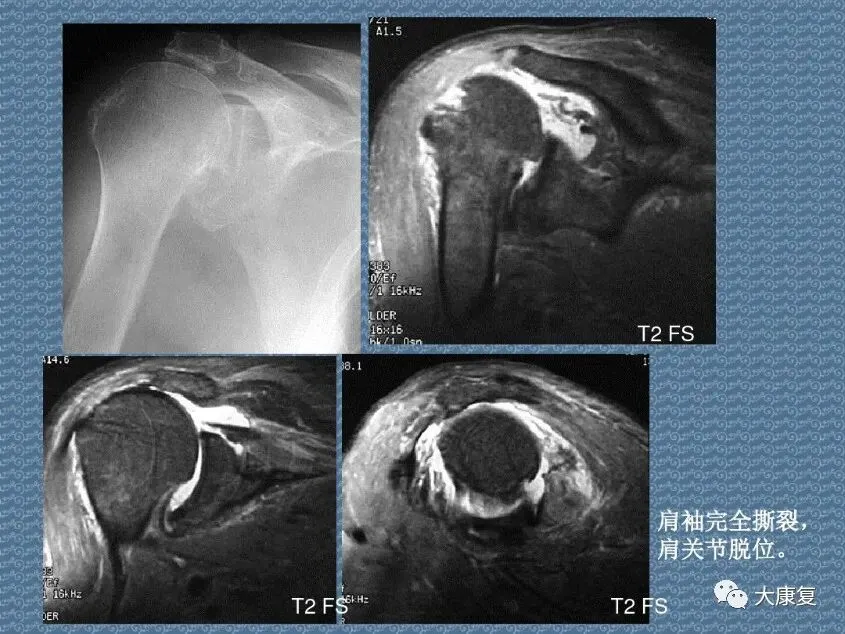

>PPT课件 | 肩关节的解剖结构和特点

PPT课件 | 肩关节的解剖结构和特点